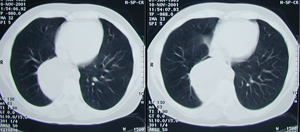

Εικόνα 4

Μετεγχειρητική οπισθιοπροσθία ακτινογραφία του θώρακος. Έχουν αφαιρεθεί οι δύο κύστες χωρίς την αφαίρεση λειτουργικού πνευμονικού παρεγχύματος. Πλήρης έκπτυξη του πνεύμονος

.